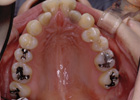

歯を抜かずに治療ができた例

治療前

治療後